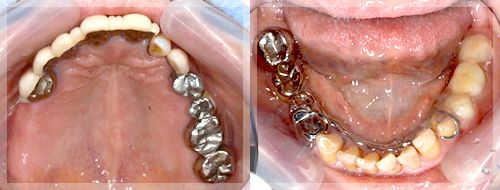

年齢:73歳

主訴:全体的に見て欲しい。特に前歯がグラグラで見た目が悪い。

初診時の診断と治療方針

初診時の状態です。前歯の見た目が悪いのはもちろんですが、歯を損失してしまっているのに加え、ご自身の歯も歯周病に罹患しているため揺れてしまっており硬い物などはあまり噛めない状態です。つまり、審美面、咬合(噛み合わせ)、歯周病、齲蝕(虫歯)、適合の悪い被せものの治療が必要で抜歯を含めて総合的に治療をしていく必要性があります。